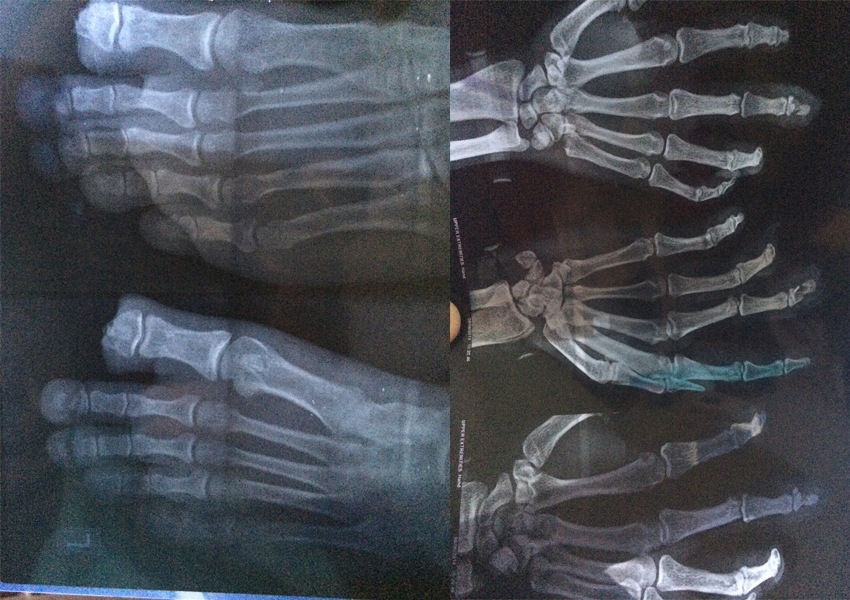

Trauma Surgery

Trauma surgery is a surgical specialty that utilizes both operative and non-operative management to treat traumatic injuries, typically in an acute setting.